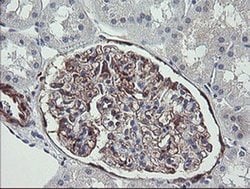

TSC22D1 Monoclonal Antibody (OTI1A5), Invitrogen™

TSC22 domain family protein, or TSC22, is a transcription factor that belongs to the large family of early response genes. This transcriptional repressor is known to act on the C-type natriuretic peptide (CNP) promoter. TSC22 belongs to the TSC-22/Dip/Bun family and is an intracellular protein that may be found in the cytoplasm or nucleus. This transcription factor is known to regulate cell growth, differentiation and cell death and is involved in modulating the transcriptional activity of Smad3 and Smad4. This protein is ubiquitously expressed in most tissues and widely in both fetal and adult tissues. It is generally expressed in aortic endothelial cells, and induced by cytokines, including TGFB. These proteins may be possible therapeutic targets of leukemia and prostate cancer.

| Immunohistochemistry (Paraffin), Western Blot | |